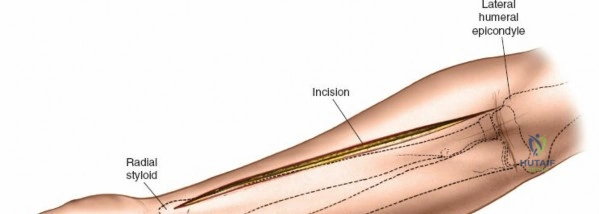

Accurate identification of surface landmarks is the first step in a successful Henry approach. Palpate the biceps tendon, a stout, taut structure crossing the anterior elbow joint just medial to the brachioradialis muscle. Next, palpate the brachioradialis itself, the fleshy muscle forming the lateral border of the cubital fossa. Finally, identify the styloid process of the radius distally. Note that when the forearm is fully supinated (the anatomic position), the radial styloid is truly lateral.

Make a straight or gently curved incision beginning at the anterior flexor crease of the elbow, just lateral to the biceps tendon. Extend this incision distally toward the styloid process of the radius. The exact length and placement of the incision are dictated by the specific pathology; the approach is highly modular, and often only the proximal, middle, or distal third of the incision is required.